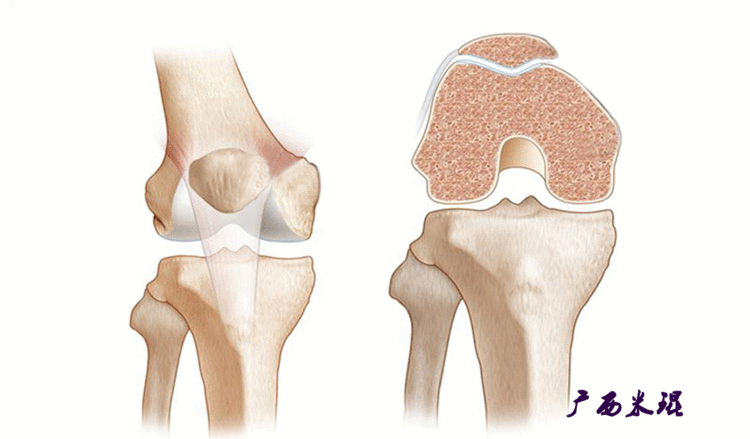

说到髌骨脱位,首先就要了解髌骨,髌骨是人体最大的籽骨,倒三角状位于膝关节前方,它的上缘与股四头肌腱相连,下缘通过髌韧带止于胫骨结节上,两侧为股四头肌扩张部,髌骨后方的凸面为光滑的关节面,与股骨下端内外髁之间的滑车凹面关节面形成关节。尽管股四头肌中的股直肌、股中间肌、股外侧肌的作用方向与髌韧带不在一条直线上,髌骨有向外突出的倾向,但因股内侧肌有向内上方牵拉作用力而使髌骨维持在正常位置。

髌骨脱位绝大部分是向外侧脱位,脱位后,髌股关节内侧的稳定结构,包括髌股关节内侧支持带、股内侧肌、内侧髌股韧带均被撕裂,导致膝关节腔内积肿,在髌骨脱位以及自行复位的过程中,髌骨内侧面与股骨髁外侧面撞击,会引起软骨损伤或骨软骨骨折,所以,千万不要把髌骨脱位当作成一个简单的疾病。